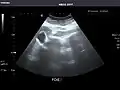

Right kidney -